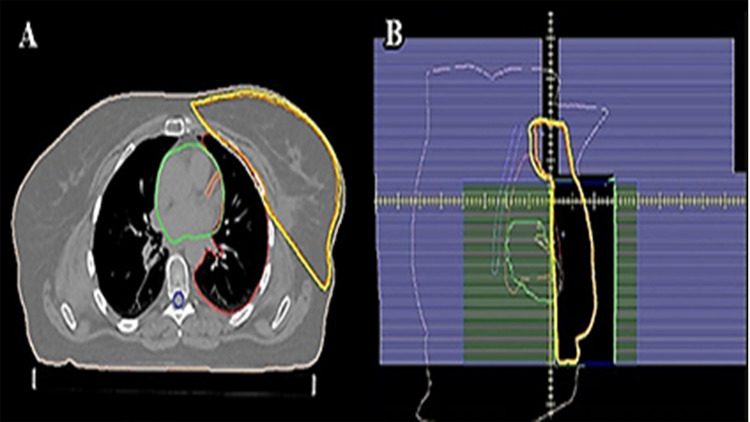

Patients and methods: A total of 15 patients diagnosed with left breast cancer with disease involved lymph nodes were included in this study. Delivering the recommended dose required the use of a linear accelerator (LINAC) with photon beams energy of 6 mega voltage (6MV). Each patient had full breast radiation using two planning procedures: intensity-modulated radiotherapy (IMRT) and three-dimensional radiotherapy (3D conformal). Following the guidelines set forth by the Radiation Therapy Oncology Group (RTOG), the planned treatment coverage was carefully designed to fall between 95% and 107% of the recommended dose. Additionally, Dose Volume Histograms (DVHs) were generated the dose distribution within these anatomical contours.

Results and conclusion: The DVH parameters were subjected to a comparative analysis, focusing on the doses absorbed by both Organs at Risk (OARs) and the Planning Target Volume (PTV). The findings suggest that low doses in IMRT plan might raise the risk of adverse oncological outcomes or potentially result in an increased incidence of subsequent malignancies. Consequently, the adoption of inverse IMRT remains limited, and the decision to opt for this therapy should be reserved for situations where it is genuinely necessary to uphold a satisfactory quality of life. Additionally, this approach helps in reducing the likelihood of developing thyroid problems and mitigates the risk of injuries to the supraclavicular area and the proximal head of the humerus bone.